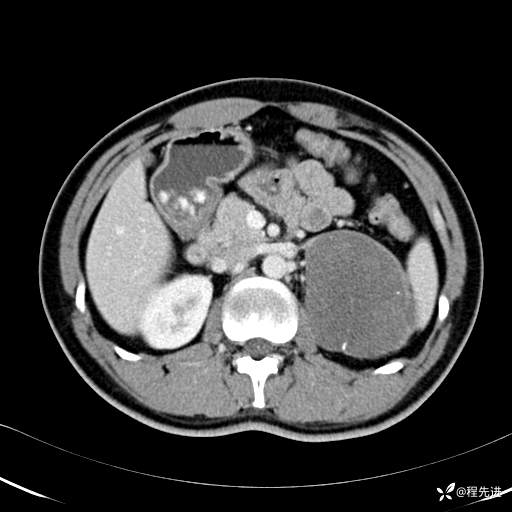

平衡期: